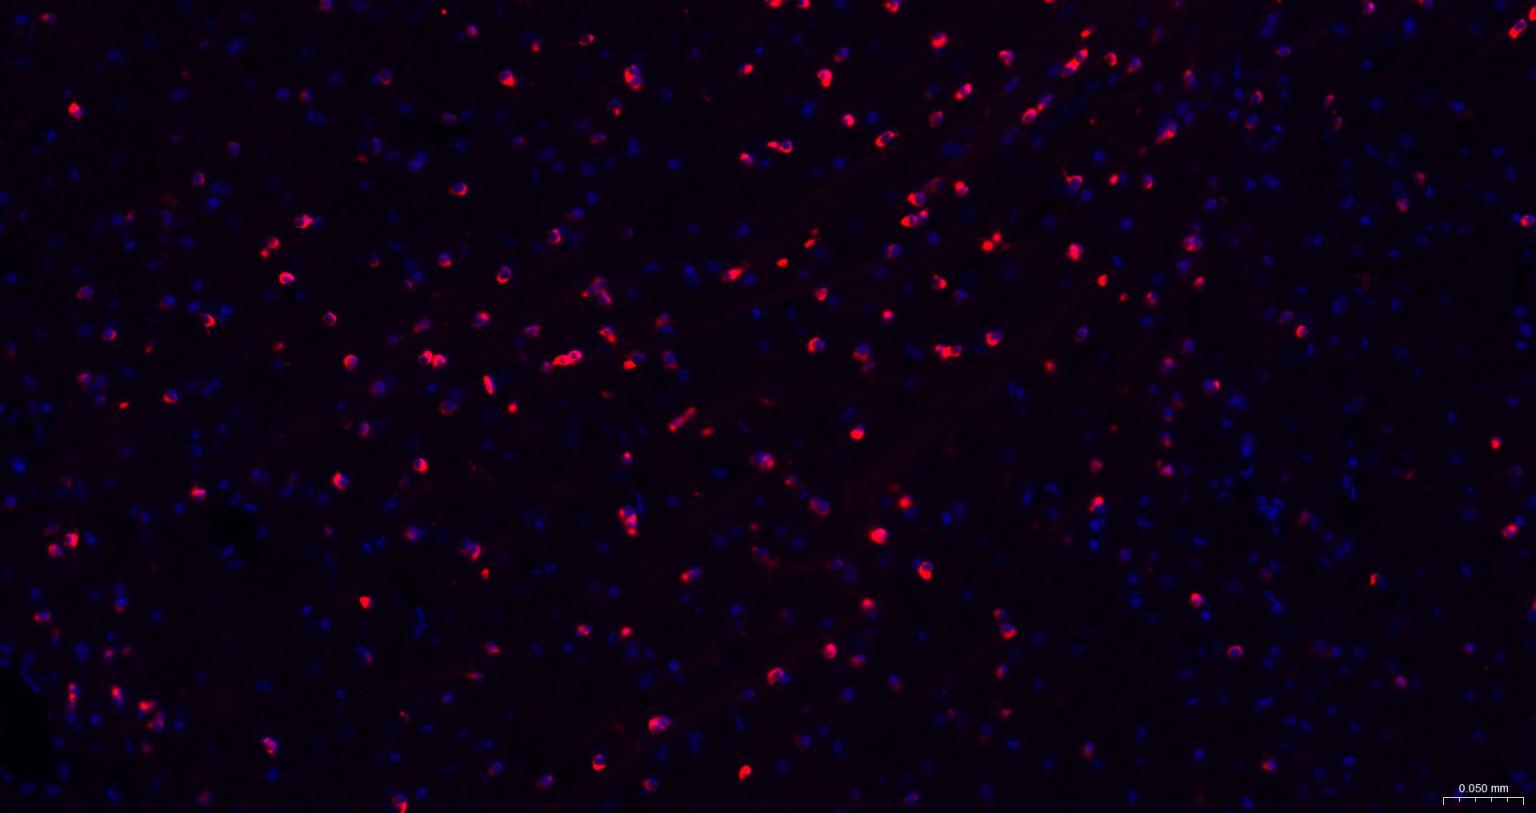

神经细胞标志物

(NMDAR1)N-甲基-D-天门冬氨酸受体(NMDAR)是兴奋性氨基酸受体亚型之一,是由NMDAR1与不同的NMDAR2亚基组成的异聚体。

The protein encoded by this gene is a critical subunit of N-methyl-D-aspartate receptors, members of the glutamate receptor channel superfamily which are heteromeric protein complexes with multiple subunits arranged to form a ligand-gated ion channel. These subunits play a key role in the plasticity of synapses, which is believed to underlie memory and learning. Cell-specific factors are thought to control expression of different isoforms, possibly contributing to the functional diversity of the subunits. Alternatively spliced transcript variants have been described. [provided by RefSeq, Jul 2008]

| IF | Human, Mouse, Rat | 1:100-500 |